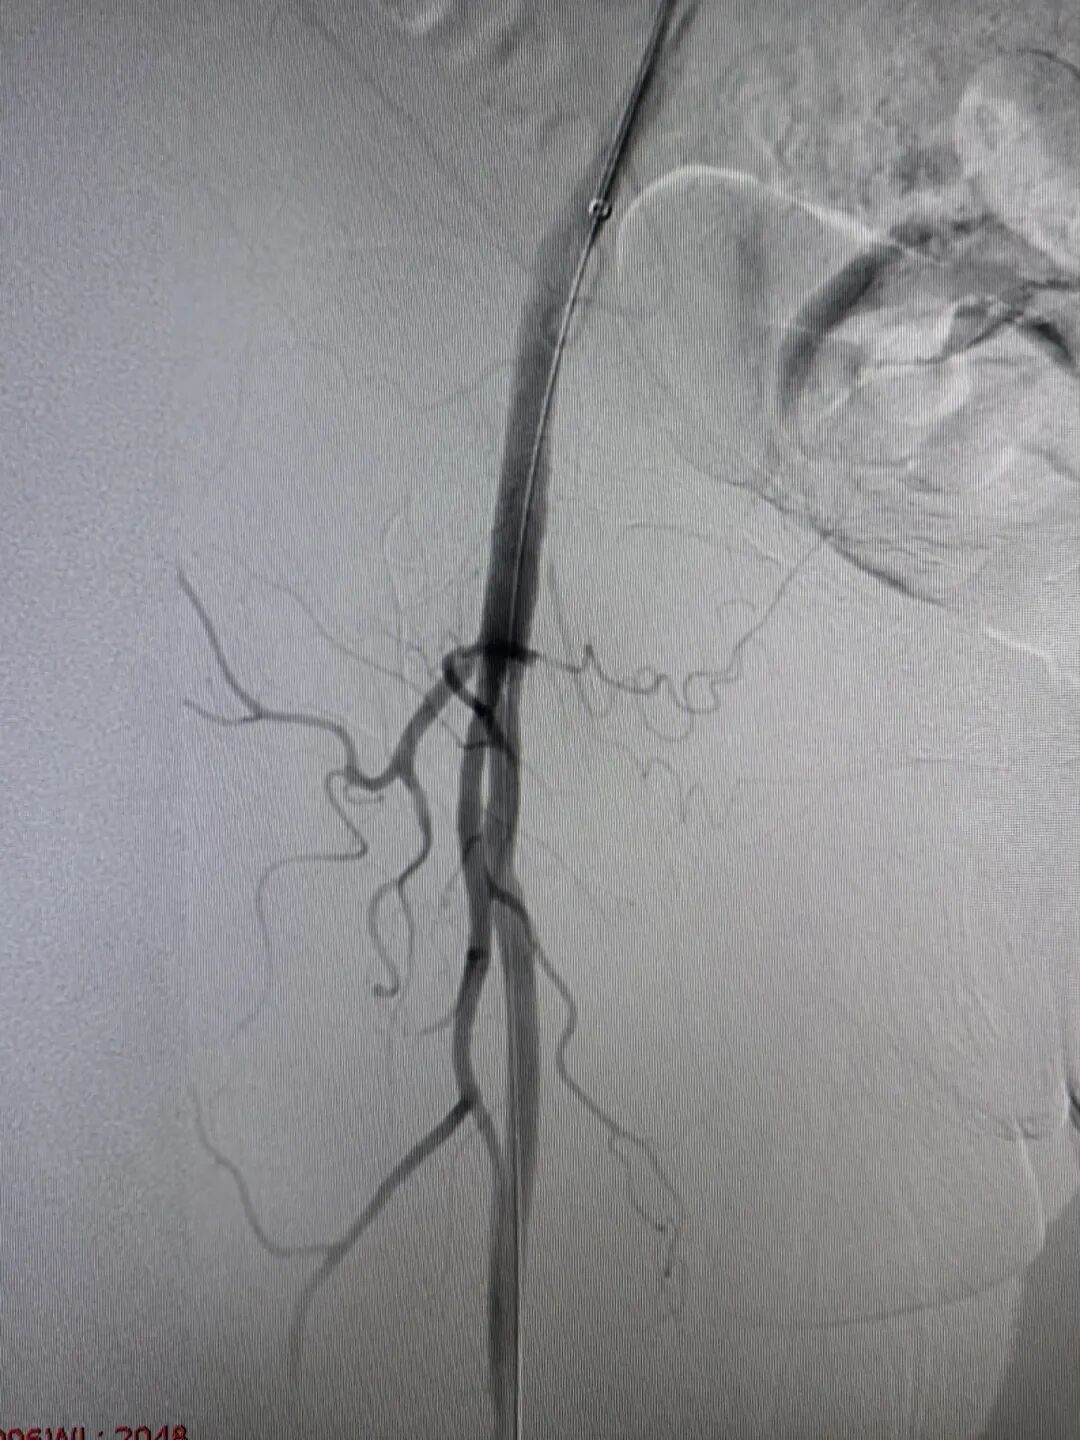

(右侧股总动脉栓塞)

“马上启动多学科协作!”急诊科立即联系介入及脑血管病科薄进保主任。医护团队在最短时间内完成术前准备,患者从急诊室直接推入介入手术室,全程无缝衔接。急诊科护士寸步不离,密切监测心率、血压、血氧;介入团队早已就位,薄主任为孙奶奶实施右下肢动脉血栓取栓术